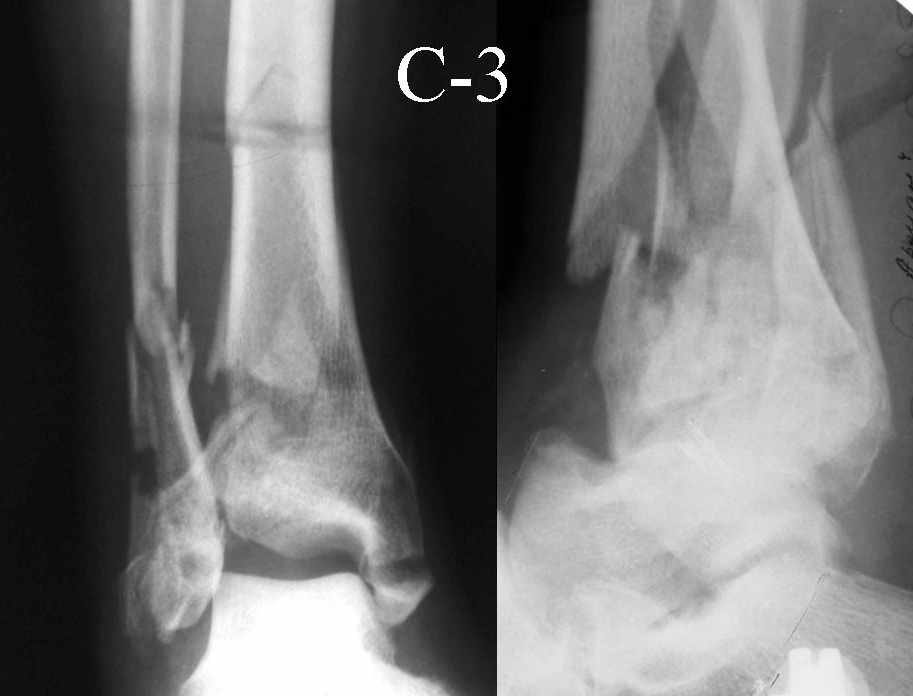

Это типичный перелом пилона, который надп лечить только открыто.Извини те что опоздал к обсуждению, но даже если вы уже оперировали больного по Илизарову это даже лучше.Посылаю картинки.

На рентгенограммах типичный перелом пилона по типу С-3. есть опыт до 100 открытых опреаций у нас в клинике. 20 примерно в год. Принцип один -все внутрисуставные переломы нуждаются в открытой репозиции и внутренней стабильной фиксации. При поступлении КТ не надо, так как получается только нагромождение костей. Истинной картины нет. Главное восстановить длину малоберцовой кости - это ключ к успеху. При поступлении меньше всего надо думать о сосудистых расстройствах, т.к. сама операция и репозиция даже сначала частичная даёт улучшение сосудитых нарушений. Причём очень быстро. Операция в 2этапа. При поступлении доступ позади наружной лодыжки, причём обязательно. После этого репозиция малоберцовой кости и фиксация пластиной 1/3 трубки под винт 3,5. Дренаж и любой аппарат наружной фиксации. Затем после спадения отёка на 5-7-10 день аппрат снимается и дугообразный разрез спереди от медиальной лодыжки 10-12 см. Главной чтобы расстояние между 1 и вторым разрезом было не меньше 7-8 см. Тогда не будет некрозов лоскутов. Таранная кость используется как матрица на неё укладываются отломки и фиксируются пицами. Ренг-контроль. Отломки лежат все отдельно, но ничего не высыпется. При переломах С-3 всегда нужна костная пластика (из крыла). Фиксация пластиной лист клевера простой или LCP. Гипс не нужен. Дренаж до 48 часов. Операция длится 3-4 часа обязательно без жгута. Посылаю примерно такой же случай.

Послала ещё два снимка, если не пройдут, пошлю ещё. Дрягин. Если есть вопросы, готов ответить.